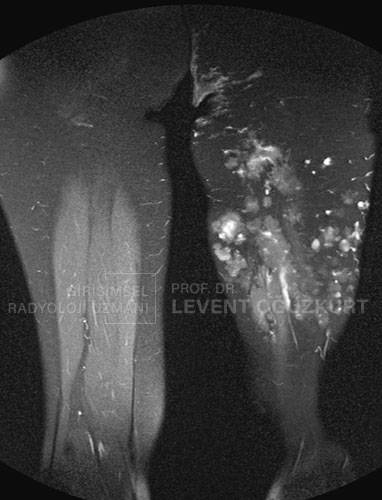

Anomral damar oluşumları deriden görülüyorsa dıştan muayene ile hastaların çoğunda tanı konabilir. Bazen dışta görünenden çok vücudun iç tarafına uzanırlar. Bu durumda radyolojik görüntüleme yöntemleri ile tanı konur. Bazen renkli Doppler ultrason ve bilgisayarlı tomografi inceleme yapılsa da tanıda MR (emar) görüntüleme en değerlidir. Düşük akımlı malformasyonda anjiyo yapılması çoğunlukla gerekmez.

Emar (MR) görüntüleme bu hastalığın tanısında en önemli ve doğru tanı koyan görüntüleme yöntemidir. Burada damar dokusunun büyüklüğü ve diğer dokular içine uzanımı çok güzel görülür.